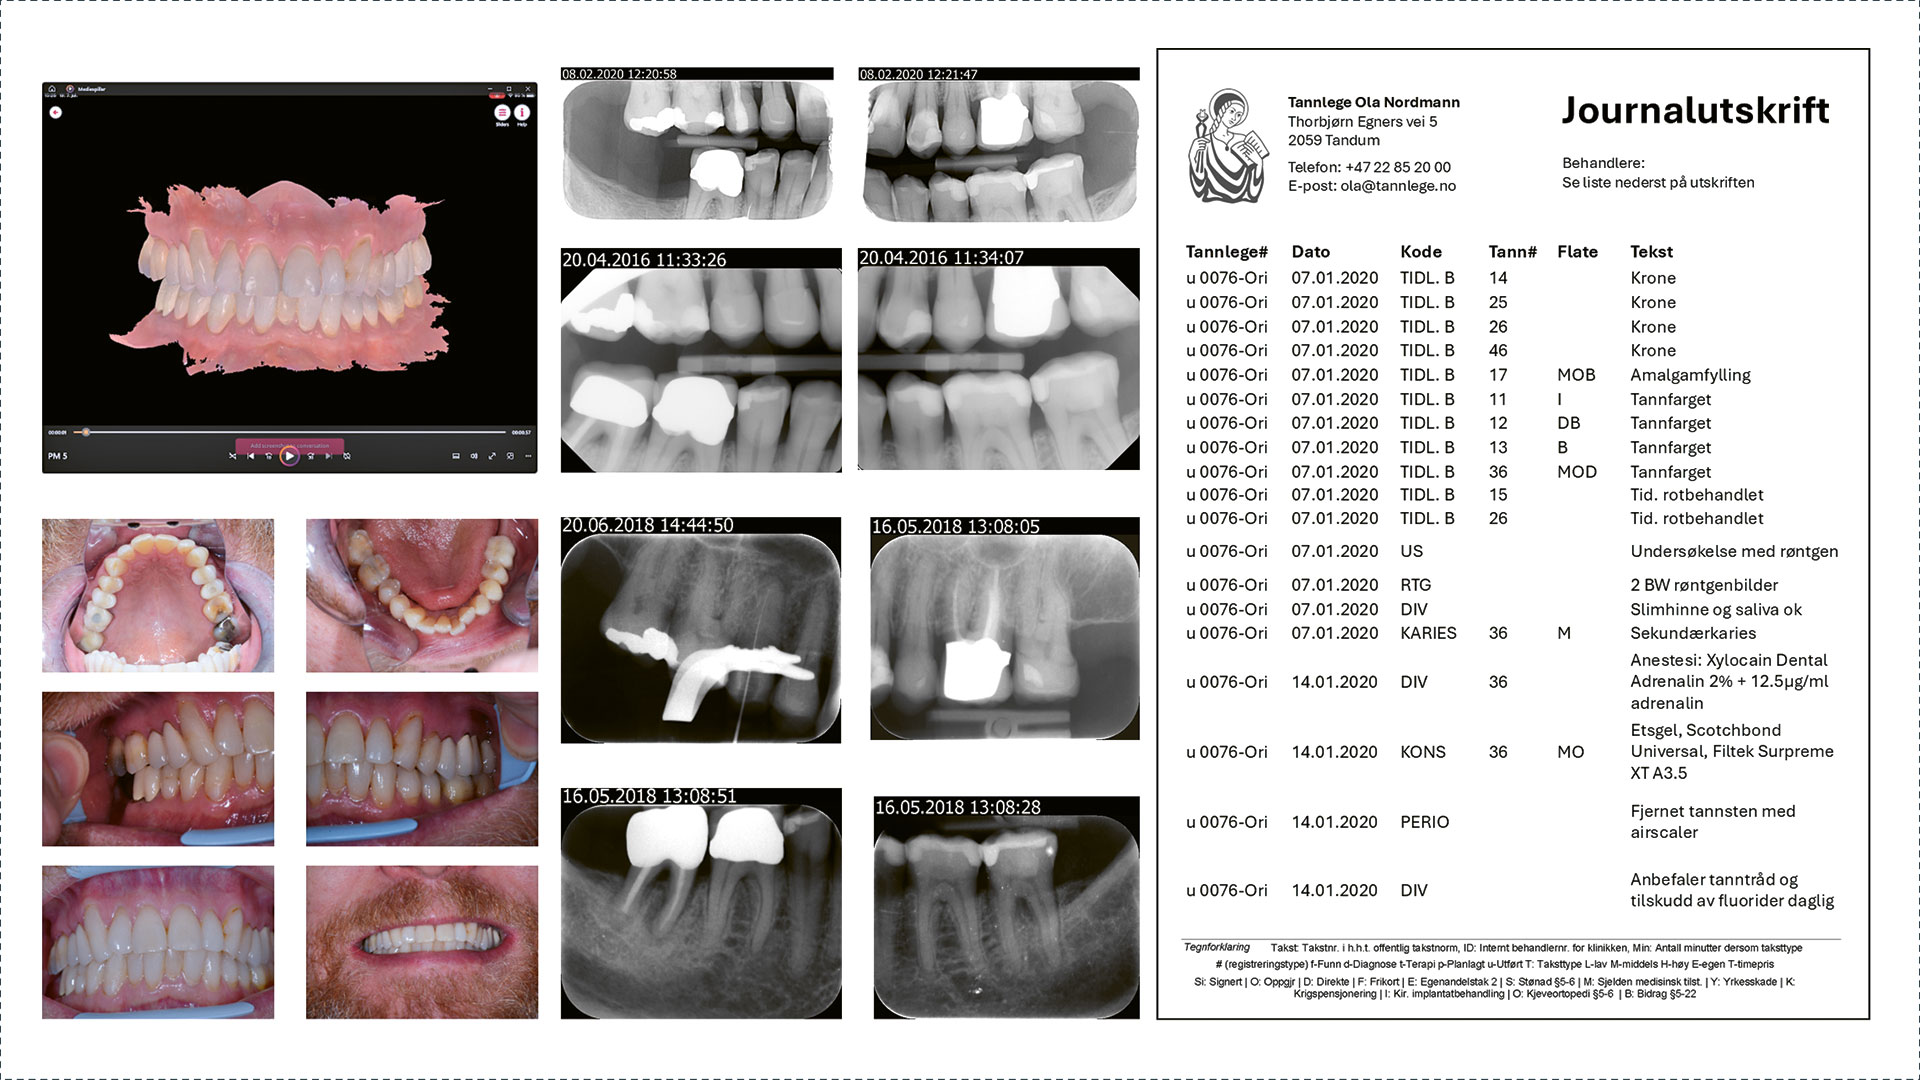

Figur 2

Figure 2. A digital patient record, consisting of written records, radiographs, clinical photographs and a digital scan of the jaws (courtesy of Ina C. Knivsberg, Norway).